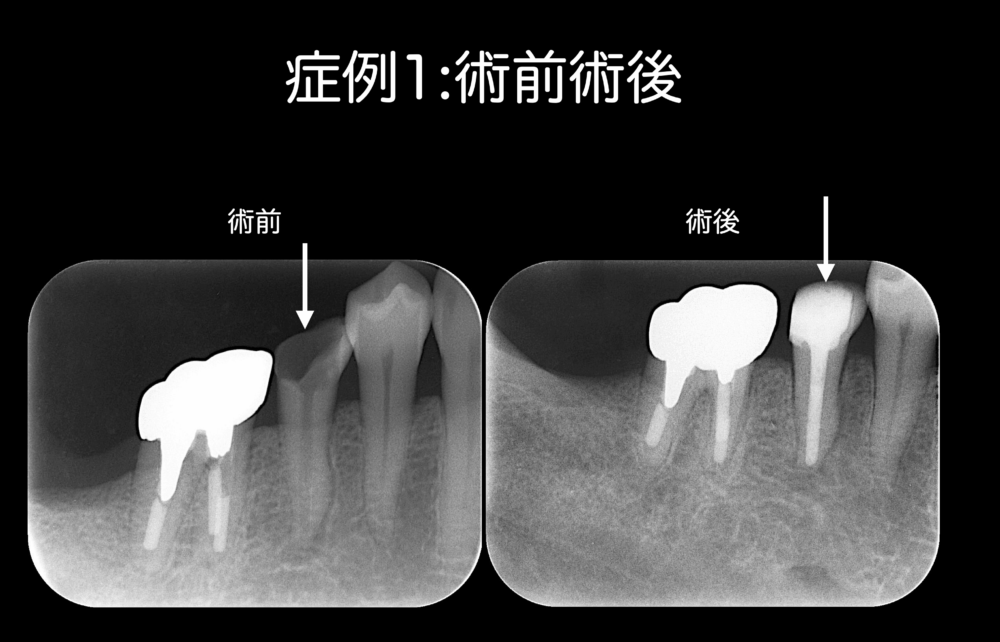

症例1:基本コンセプトを遵守している根管治療を行って痛みが改善したケース

根管治療中に痛みが出たため蓋をしなかった患者さんです。

根管治療をスタートさせて3ヶ月くらい経過しますが、痛みが出ているため蓋も薬も詰めていない状態でした。

無菌的環境下で、洗浄・貼薬を行い、根管の中をベストな状態にしたところ、痛みは改善しました。洗浄剤の抗菌効果が功を奏し、痛みが取れました。

この症例は、蓋をしていても痛みはありません。痛みがないから蓋をしたわけでもありません。蓋の役割は細菌感染を予防することにあります。特別な場合を除き、根管治療の間に蓋はした方が良いです。